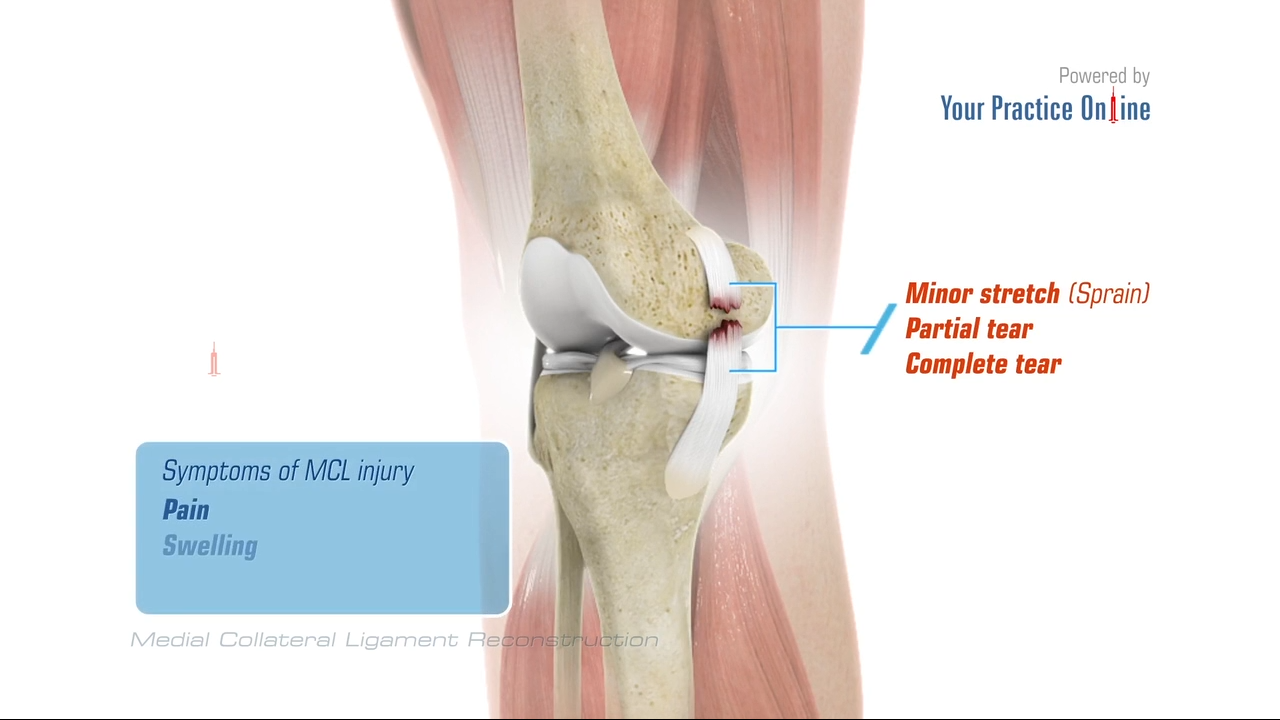

There are two primary types of mcl surgery: While most mcl injuries can resolve without surgery, there are instances where surgery is the best treatment option. You’ll need to raise your sore knee when you put ice on it, keep weight off the joint, and protect and compress the injury with a knee brace or elastic bandage.

Treatment options for an mcl sprain. The surgery will either repair or reconstruct the mcl. A total rupture of the mcl usually doesn’t require surgery.